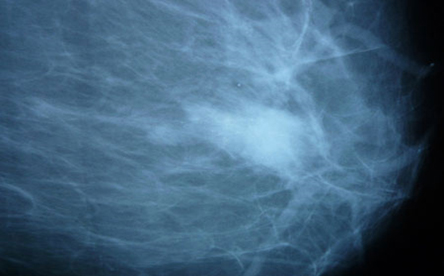

乳腺癌的检查

乳腺癌是一种多发于女性身上的疾病,80%的乳腺癌病历并没有明确的家族史。所以,即使你的家族中没有乳腺癌的病史,也绝不可以掉以轻心。同时,那些有家族病史的女性,应该更加密切关注自己的乳房。建议35至40岁开始,每1年至1.5年做一次乳腺癌检查。

- 超声波检查(乳腺)

- PEM(乳房专用PET)